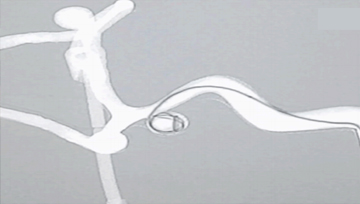

3) 3D 혈관 시뮬레이터 및 투시 조영술 X-ray

3D 혈관 시뮬레이터는 투시 조영술 X-ray 장비와 호환기능을 이용하여 최적의 영상을 시뮬레이션할 수 있습니다. 투시 장비를 이용하여 인체 모든 부위를 X-ray 영상으로 나타낼수 있습니다.

혈관중재시술에서 사용되는 가이드와이어, 스텐트, 코일 등은 3D 혈관 시뮬레이터를 통해 시연, 데모 될 수 있고, 학생들에게 직접 시뮬레이션할 수 있는 기회를 갖게 됩니다.